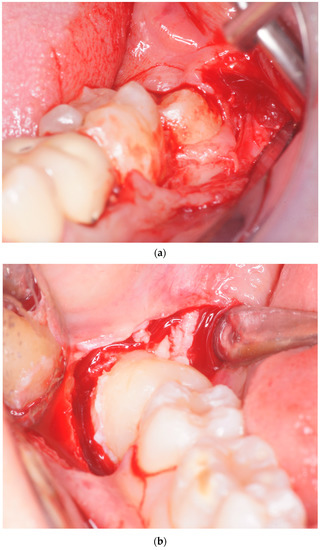

2.2. Surgical Procedure